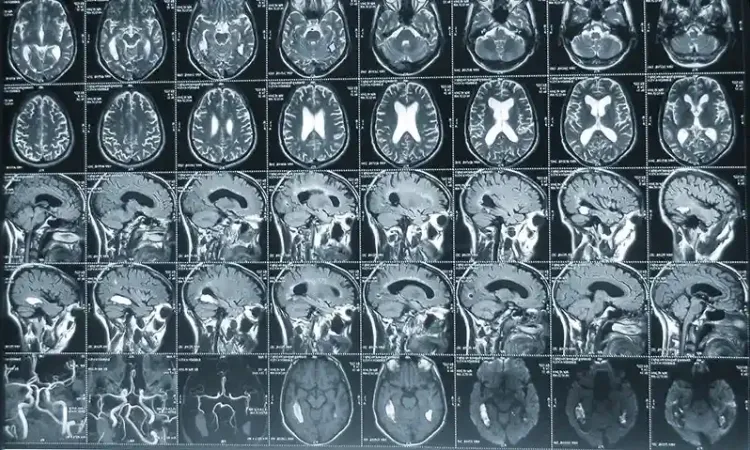

Эффект МРТ основан на ядерно-магнитном резонансе. Пациента помещают внутрь томографа. Аппарат создает мощное магнитное поле, под воздействием которого атомные ядра водорода, содержащиеся в клетках организма, начинают вибрировать. Разные структуры отдают разное количество энергии. Это фиксируется томографом, который делает снимки нужной области в нескольких проекциях. Полученные срезы при помощи компьютерной программы объединяются в единое трехмерное изображение, на котором четко видны очаги поражения.